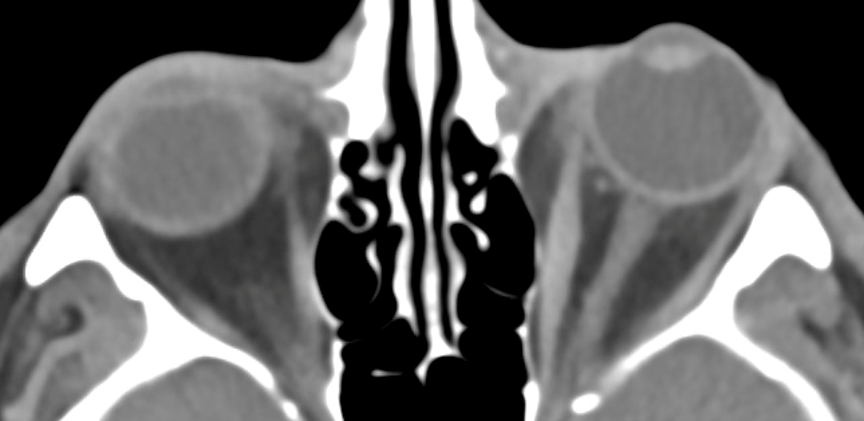

Axial orbital imaging prior to orbital decompression and teprotumumab infusion shows left-sided exophthalmos and enlargement of the left superior rectus. Source: NYU Langone Health